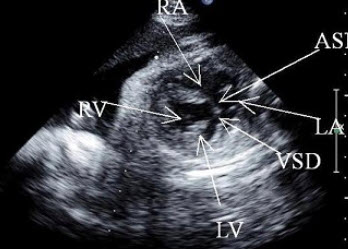

胎儿心脏超声检查如图,最可能的诊断是()

A.法四